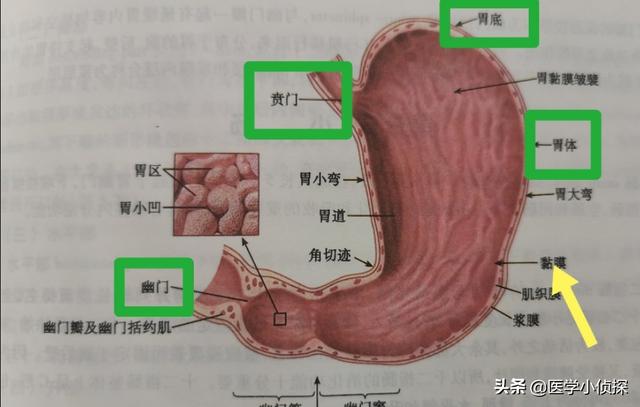

ご存知のように、胃は私たちの体の中にあり、消化器系の重要な器官である。通常、胃は4つの部分に分けられ、心窩部に近い部分は「胃」と呼ばれる。ふんもん心窩部平面の上方、左上に広がっている部分は胃底と呼ばれ、眼底から角切欠きに至る胃の中央部分はコーポラス最終胃の下縁と幽門の間の部分は幽門部と呼ばれ、臨床的には幽門部とも呼ばれる。胃窦。

胃がんの好発部位は、肛門、噴門、胃体部である。対応する胃壁粘膜層の上皮細胞いくつかの悪性腫瘍の後に起こる胃の癌性変化は胃癌と呼ばれる。